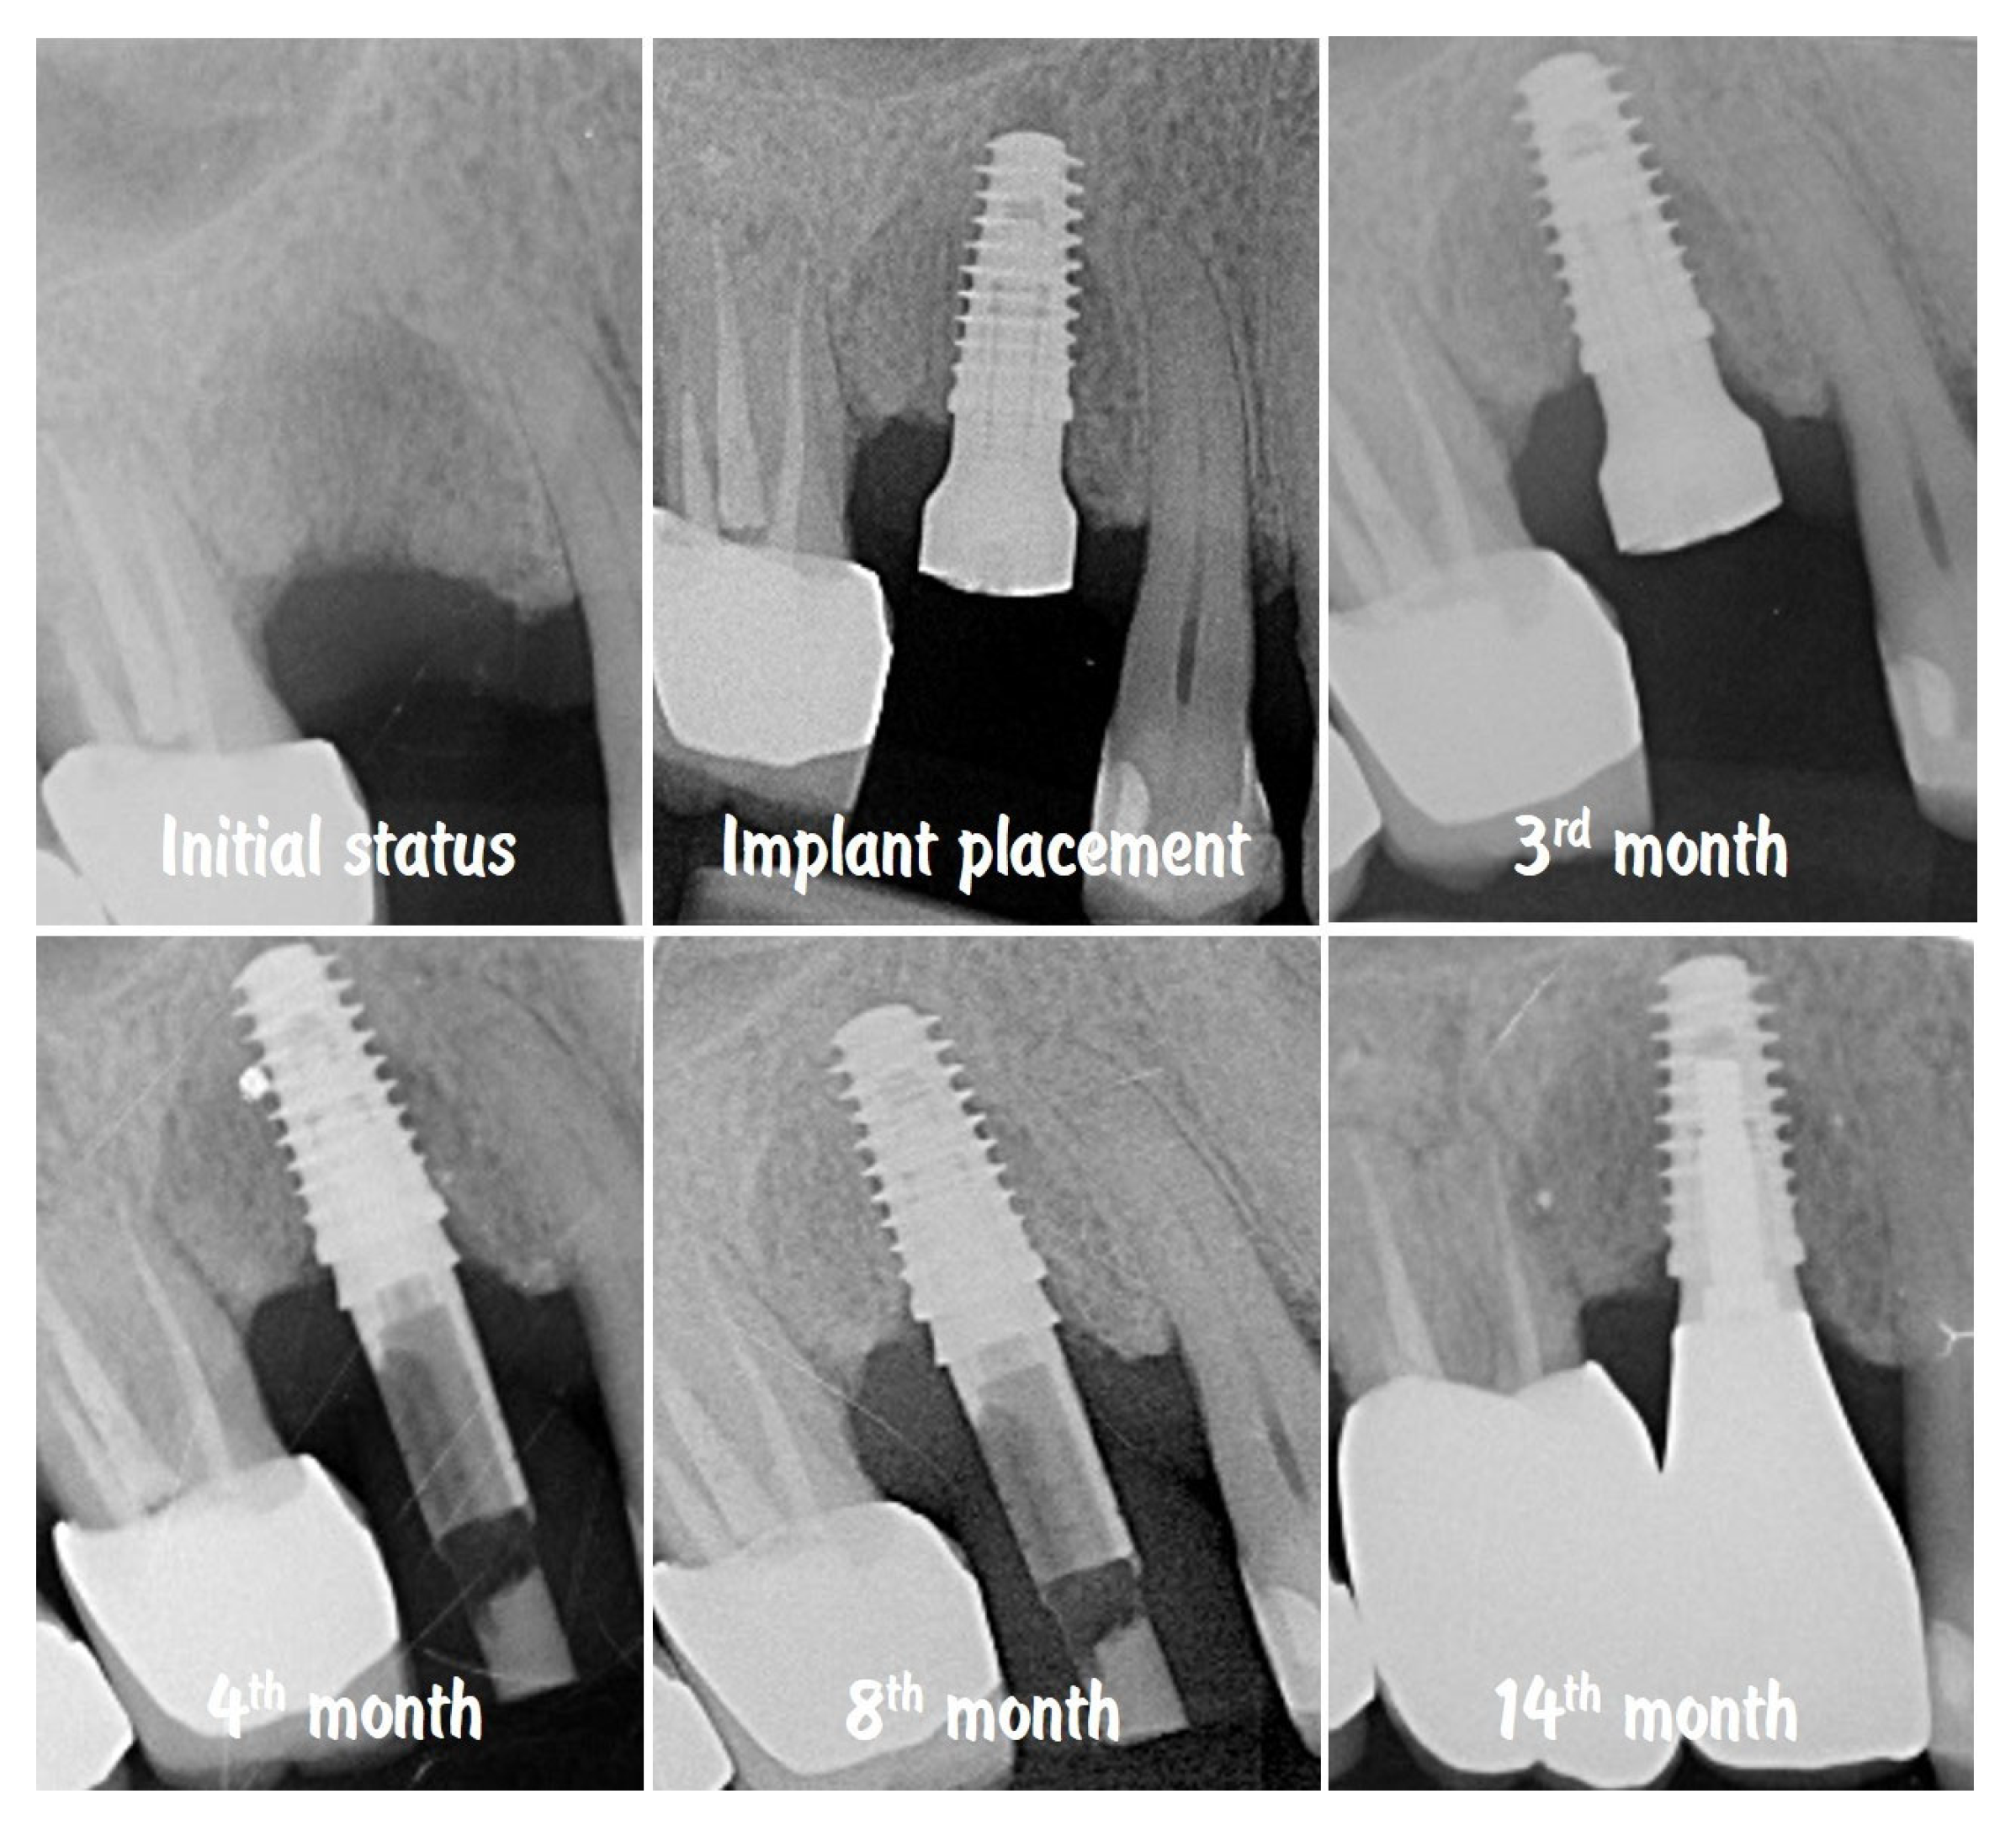

The comparison of the X-rays shown in Figure 19 presents the stability of the crestal bone levels prior to implant placement to the 14th month after implantation. The combination from minimally invasive implant site preparation, provision of an adequate peri-implant soft tissue thickness, and proper emergence profile of the implant-supported restoration ensured the protection of the bone volume without signs of remodelling or resorption.

Figure 19.

Stability of the crestal peri-implant bone.